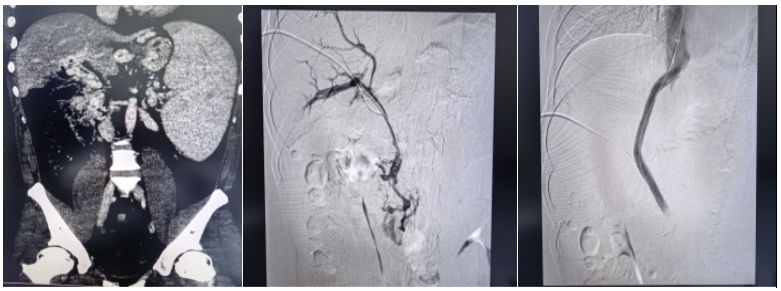

近日,中南大学湘雅三医院放射介入团队在副主任(主持工作)梁琪的带领下,成功完成一例国内罕见的超高难度经颈静脉肝内门体分流术(TIPS)。该手术突破介入诊疗临床极限,为被致命出血风险困扰7年的患者重建生命通道,彰显了医院在复杂门静脉高压、疑难血管疾病介入诊疗领域的实力。

此次手术被业内视为介入领域的“极限挑战”,核心难点在于患者极为罕见的血管条件:门静脉主干完全闭塞,门脉海绵样变,脾静脉与肠系膜上静脉广泛血栓充填,常规TIPS手术缺乏有效流入道,标准穿刺路径完全失效。在血管解剖结构破坏、解剖标志模糊、血栓弥漫充填的极端条件下,从零构建肝内分流通道,对术者的操作精度、临床经验与应急处置能力均提出极高要求。

“没有通道,我们就为生命开辟一条通道。”面对患者与家属的殷切期盼,梁琪带领吴作为、骆雷等核心团队成员毅然迎难而上。术前,团队反复研读影像学资料,全面评估血管条件与手术风险,制定了周密的个体化手术方案。术中,团队凭借深厚的介入诊疗功底,沉着操控、精准穿刺,在闭塞多年的血管中耐心探查、精细开通,成功将支架置入门静脉主干并建立肝内分流道,显著降低门静脉压力,从根源上解除致命大出血风险,实现微创、安全、高效救治,疗效远超家属预期。